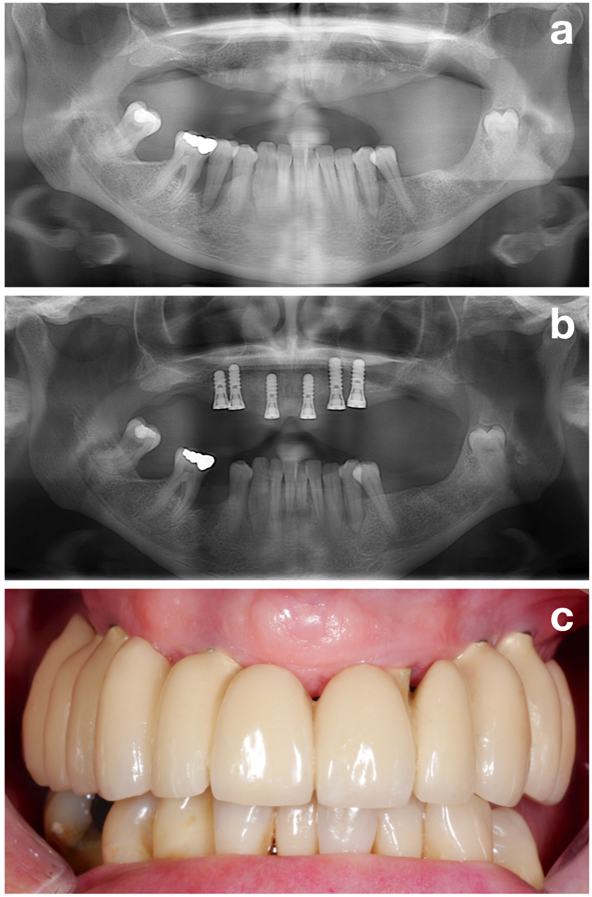

Figure 2. A stable periodontal situation should be established prior to implant installation. Patient prior to periodontal treatment (a), after periodontal treatment and implant installation (b), and after prosthetic restoration (c). © Dr. K. Bertl

The first part (i.e., the pre-treatment phase) aims to perfectly prepare the patient for the actual implant installation by evaluating all potential risk factors but focusing on one of the most important ones: establishment of a stable periodontal situation (Figure 2).